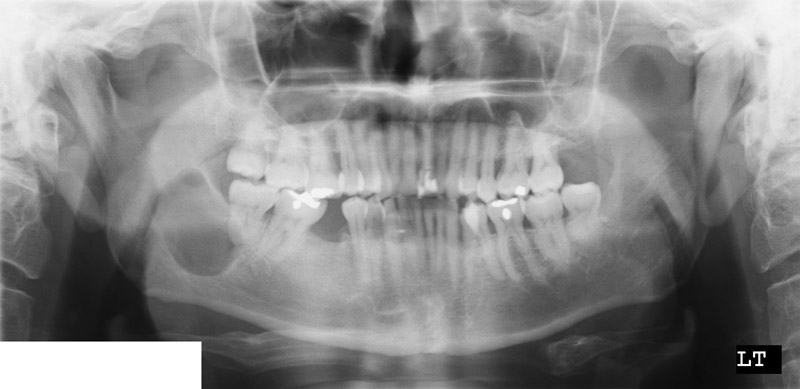

Panoramic view

Imaging:

• The panoramic view and the CT scan demonstrated a unlilocular, well demarcated, radiolucent lesion in the posterior aspect of the mandible. The rim of the lesion is smooth. There is no calcification at the center of the lesion.

• The mandible, particularly the posterior aspect, is more affected than the maxilla.

• Well-defined, round or ovoid unilocular ardiolucency with smooth margin and frequently associated with an unerupted tooth.